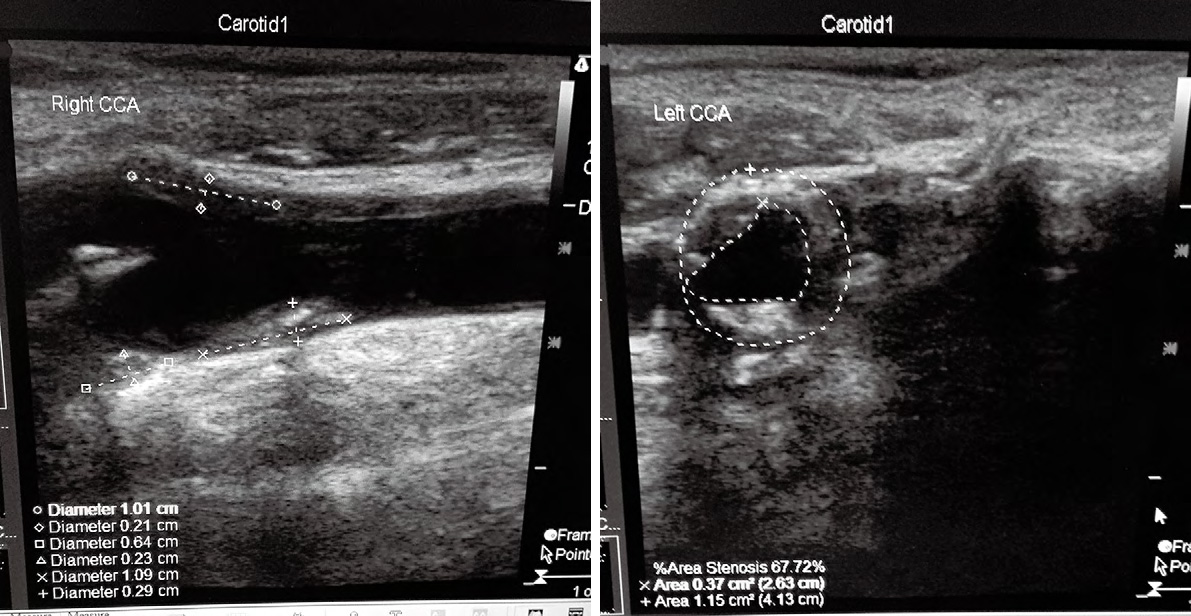

下图1、2是114例患者中的典型病例,老年男性,主诉为头昏伴双手麻木不适数月,加重1周来我院神经科门诊就诊,予TCD和颈动脉超声联合检查进行早期筛查。检查结果如下:

图1TCD提示:双侧颈内动脉末-大脑中动脉流速显著增快,伴频谱紊乱,涡流形成, 考虑双侧颈内动脉末-大脑中动脉狭窄;压颈试验后证实右侧大脑前动脉、双侧大脑后动脉代偿;脑血管弹性减退

图2 颈动脉超声提示:双侧颈动脉及椎动脉硬化;双侧颈部数个多发性动脉粥样硬化斑块形成;右侧颈总动脉球部斑块处管腔轻度狭窄;左侧颈总动脉球部斑块处管腔中度狭窄

颈动脉易损斑块合并狭窄更易发生脑卒中[4],上述病例也可证实,TCD 联合颈动脉超声可以起 到协同互补的作用,可以对颅内外动脉狭窄以及 斑块的情况做详细的研究记录,并能了解脑血流 动力学情况,可提高疾病诊断率[5]。为临床选择 实施治疗方法提供客观依据。当TCD检查结果 提示血流速度减慢时,可见于狭窄前后的血管, 也可见于探测角度不良,血管扩张等情况,此时 就需要整体的检查颈部和颅内血管,寻找原因, 才能判断血流速度减慢的意义。